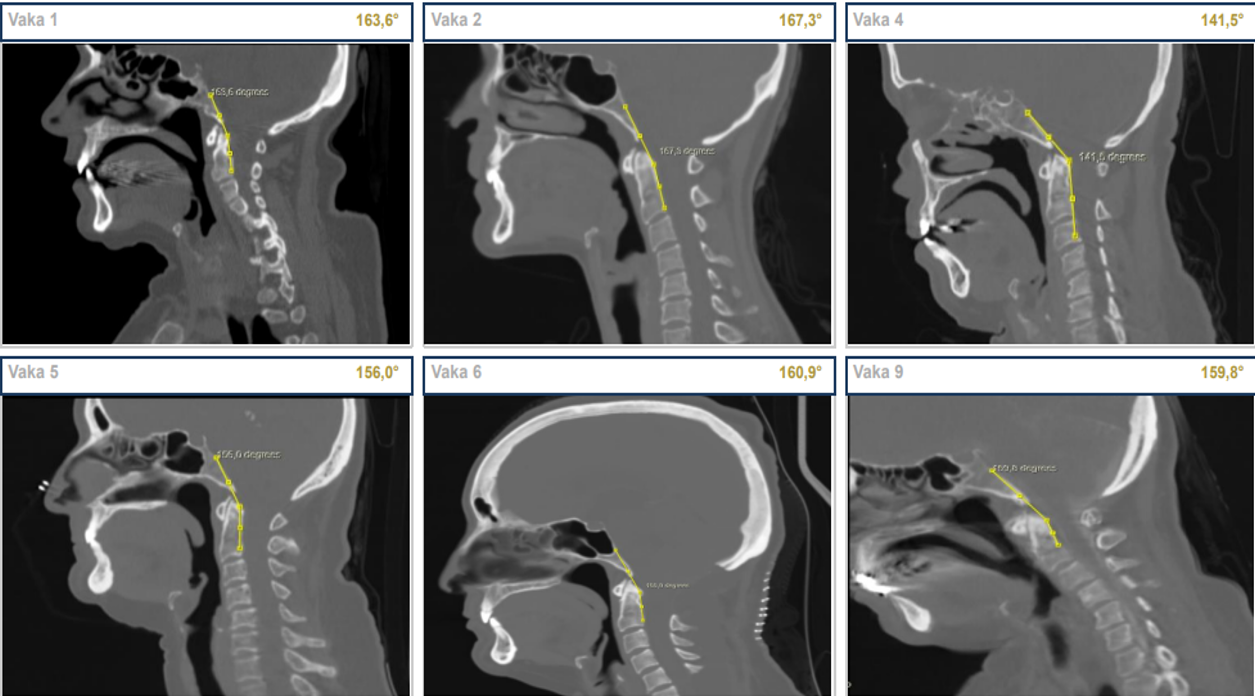

Yöntemler: Mart 2020–Şubat 2026 tarihleri arasında SİH tanısı doğrulanan dokuz hasta retrospektif olarak değerlendirildi. Bern skoru (0–9), pontomezensefalik açı (PMA), mamillo-pontin mesafe (MPM) ve klivoaksiyel açı (CXA) sistematik olarak ölçüldü. Hastalar Schievink sınıflamasına göre dört alt tipe ayrıldı; klinik yanıt NRS tabanlı üç kademeli sınıflamayla, komplikasyonlar Clavien-Dindo sistemiyle değerlendirildi.

Kranyal MRG bulguları Bern SİH kranyal MRG skorlama sistemi7 kullanılarak sistematik olarak değerlendirildi (pakimeningeal kontrast tutulumu, venöz sinüs distansiyonu/VDİ, subdural sıvı koleksiyonu, suprasellar sisterna, prepontin sisterna ve hipofiz büyümesi; toplam 0–9 puan). PMA, sagittal T1 MRG’de mezensefalon dorsal yüzeyi ile pons ventral yüzeyi arasındaki kesişim açısı olarak ölçüldü (normal 55–75°; EKY yanıt eşiği ≥40°).9 MPM, midsagittal T1’de mamiller cismin alt ucundan ponsa dik mesafe olarak tanımlandı. CXA, sagittal BT görüntülerinde klivus posterior yüzeyi boyunca çizilen hat ile C2 aksı arasındaki açı olarak ölçüldü (normal >135°). VDİ, orijinal tanımına uygun şekilde kaydedildi.13 Tüm ölçümler tek bir araştırmacı tarafından retrospektif olarak yapıldı. PMA ve MPM ölçüm teknikleri Şekil 2’de gösterilmektedir.

Ölçüm yapılabilen yedi hastada (Vakalar 1–5, 8–9) preoperatif PMA 27,4°–37,5° arasında dağıldı; tüm değerler normal referans aralığının (55–75°) ve Wu ve ark.’nın EKY yanıt eşiğinin (≥40°)9 belirgin altındaydı. MPM 3,3–4,6 mm (normal ~9–12 mm), CXA 141,5°–167,3° arasında saptandı (Şekil 3). Venöz distansiyon işareti (VDİ) sekiz hastada (%88,9) pozitifti. Postoperatif görüntüleme mevcut olan dört hastada (Vakalar 1, 2, 3, 9) en belirgin PMA artışı Vaka 3’te gözlendi (+17,4°); ancak hiçbir hastada normal referans aralığına ulaşılamadı. Vaka 9’da üç ardışık EKY sonrasında klinik iyileşme elde edilmesine karşın PMA hafifçe geriledi (37,5°→34,6°). Tüm ölçümler Tablo 2 ve Tablo 3’te özetlenmiştir (Şekil 4).

Bern skoru, PMA ve etiyolojik alt tip arasında tutarlı kümelenme gözlemlendi: CVF olguları (Vakalar 6–7) en yüksek Bern skoru (9) ve ölçülemeyen PMA ile ağır fenotipi temsil ederken, kriptojenik olgu Vaka 3 en düşük Bern skorunu (2) ve en belirgin radyolojik iyileşmeyi (%17,4° PMA artışı) gösterdi. İstatistiksel analiz özeti Tablo 4’te verilmektedir. Prepontin ve suprasellar sisterna ölçümleri Şekil 5’te sunulmaktadır.